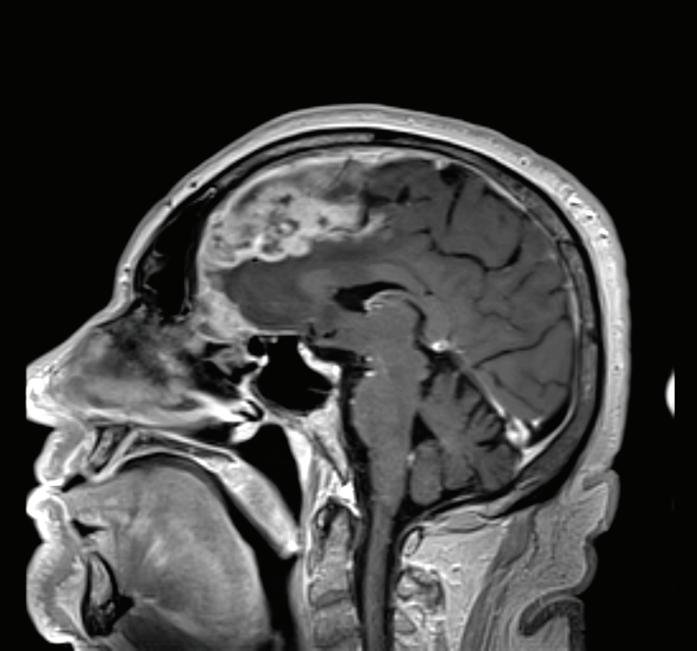

ПРЕДНА КЛИНОИДЕКТОМИЯ В. Наков

74 РЯДЪК